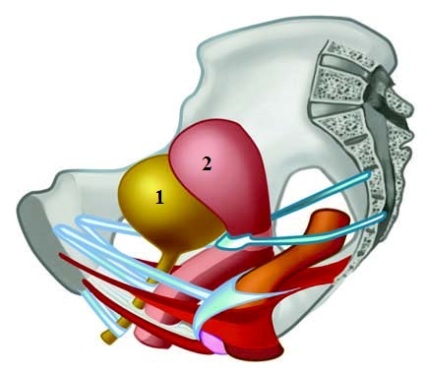

Анатомия малого таза: детальные схемы и изображения